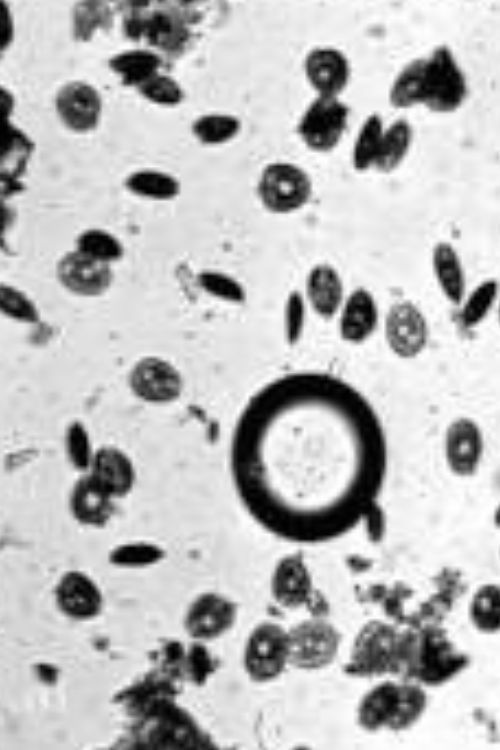

Anthony van Leeuwenhoek документальный